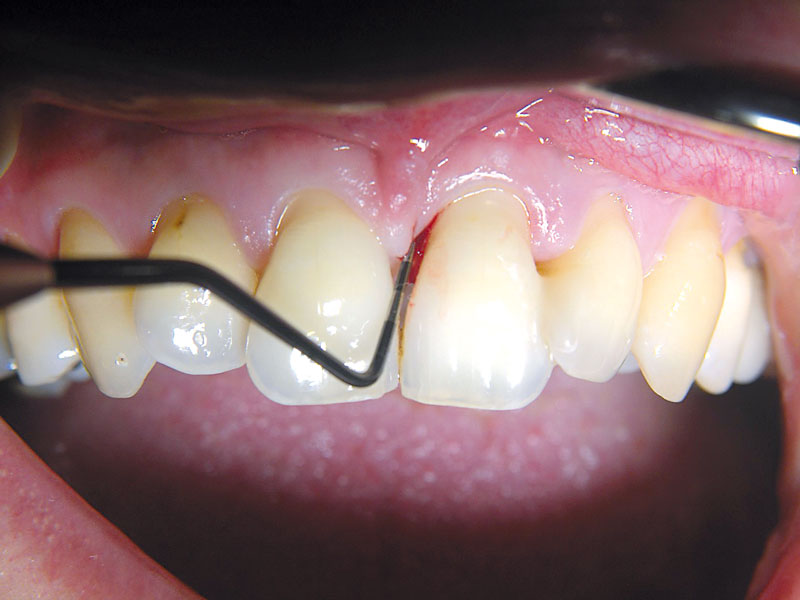

03/11 - Pre-surgical probing.Non-contained intrabony defect treated using cerabone®, collprotect® membrane and Straumann® Emdogain® - Dr. T. Schwaar (2)